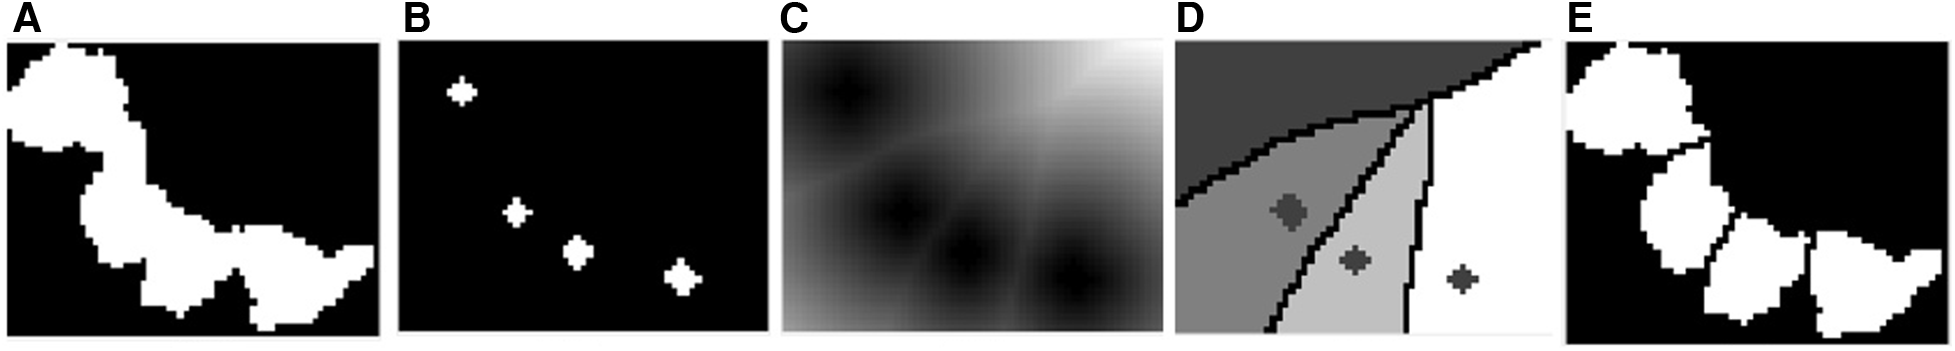

In this study, it was necessary to segment the following objects: the amastigotes and the nuclei and cytoplasm of macrophages. The S channel image was selected because it could show the differences between these parts clearly enough. Here, the nuclei and amastigotes appeared as the brightest region in the image; therefore, they could be deemed as belonging to a single class but could be differentiated by their dimensions afterward. The cytoplasm appeared as a slightly dark gray region and the background of the image was practically black. These image characteristics led us to propose a multilevel thresholding segmentation with two thresholds to separate these different regions into three classes.

Otsu's method (25) is a widely used technique for image thresholding. This method found the optimal threshold by maximizing the between-class variance of pixel values, which effectively separates foreground and background regions. Thus, to find the thresholds that separated those three regions, we used the MATLAB built-in function called multithresh, which is an extension of the original Otsu method for multilevel thresholding. Figure 4A shows the histogram corresponding to the pixel distribution of the image Saturation channel and Figure 4B shows the result of applying this method on the S channel image. Once the segmented image was obtained, the next step was to separate these regions to obtain the binary mask corresponding to each class.

3.4.1 Nuclei segmentation

After obtaining the binary mask of parasites and nuclei regions, morphological operations were performed on this mask to separate them and improve the segmentation of the parasites. First, the morphological opening operation was carried out with an approximately disk-shaped structuring element (SE) with a radius of 3 pixels to smooth the contours of nuclei and parasites, break narrow isthmuses, and eliminate thin protrusions. This radius size was defined based on the mean size of the amastigotes and on the resolution of the acquired image. Then, a morphological hole filling operation was applied to fill any “holes” caused by the thresholding process, and the objects that fell in the border of the image were removed. Finally, to separate the amastigotes from the nuclei, the size of the connected components (CCs) was analyzed by means of an area histogram; then, those objects with an area greater than 10,000 pixels were considered nuclei and the rest were considered as possible amastigotes, the binary masks of which would be refined in a further processing that will be described in a later section. This process is shown in Figure 5.

Figure 5. Nuclei segmentation. (A) Binary mask of the nuclei and parasite regions. (B) Binary mask of the parasite and nuclei regions after applying the morphological opening operation to fill holes and clear borders. (C) Binary mask of the nuclei regions. (D) Binary mask of the parasite regions.